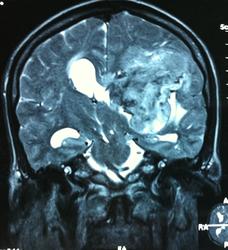

Начало вот здесь http://www.radiomed.ru/cases/kt-gms-obemnoe-obrazovanie-levoi-gemisfery-bolshogo-mozga-vnutrizheludochkovaya-meningioma. Пациент оперирован (меня сначала дезинформировали по поводу операции), перед операцией состояние ухудшилось, возникла правосторонняя гемиплегия, которая осталась и после декомпрессии. МРТ, КТ снимки и выписку предоставила супруга пациента, снимал на iphone, простите за качество, дисков с исследованиями не записывали. Надеюсь вопрос по данному случаю исчерпан.

Т2

И Вы считаете, что эта опухоль имеет интравентрикулярную локализацию?

Изначально по КТ я так предпологал, а теперь на 100% уверен, разве МРТ это не показало? Гистологически - менингиома, опухоль мозговой оболочки. Покажите, пожалуйста, образование где-нибудь прилежит к костям, где есть мозговая оболочка? Я не вижу, зато отчетливо вижу в левом боковом желудочке из оболочек сосудистого сплетения. Что вас еще смущает? По-моему, предостаточно фактов, чтобы развеять все сомнения.

Мне видится так. Иначе в данной локализации просто неоткуда расти оболочечной опухоли. На контрольной КТ, после декомпрессии, когда срединные структуры стали действительно срединны, правое обызвествленное сосудистое сплетение видно отчетливо, а левое, где оно? Ведь если бы образование компремировало, то после операции, когда часть мозга пролабировало в трепанационное отверстие мы бы увидели и левое сосудистое сплетение, но оно интимно связано с образованием и даже "потянулось" за ним в сторону декомпрессионного отверстия, потому что это и есть "росток" откуда выросла опухоль.

У меня вопрос (извините, если тупой - я-не волшебник, я только учусь=) - мне кажется, что в центре образования есть участки пустоты потока (сосуды), а разве менингиома склонна к такому неоангиогенезу? просто прочитала все вышенаписанное, вроде полностью согласна, но как вариант закралась мысль о сосудистой опухоли из сплетения бок.желудков. Если я совсем не права, прошу пояснить. Хочется все понимать уже на первых годах работы.) Заранее благодарю.